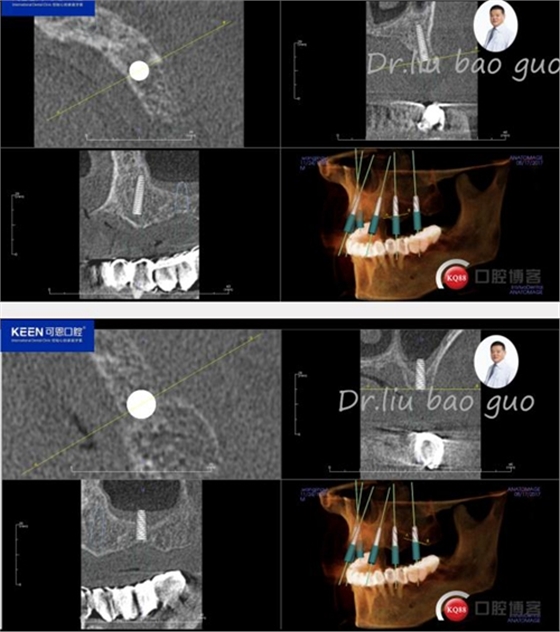

手術(shù)前種植軟件設(shè)計(jì)方案